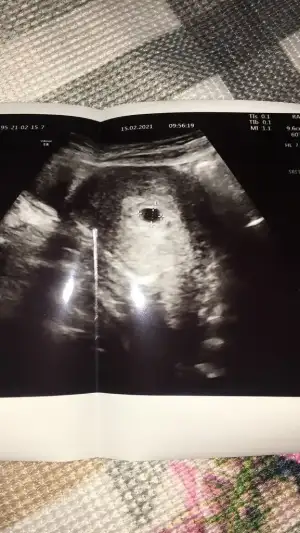

Sağlıcakla kucağına da almayı nasip etsin rabbim5 Hafta 3 günlükmüşüz.. Doktordan geliyoruz herşeyi normal dedi.. 18 haftaya kadar kilo almıyoruz dedi sağlıklı besleniyoruz.. Allah isteyen herkese nasip etsin..![]()

Maşallah canım sağlıkla kucağına da al5 Hafta 3 günlükmüşüz.. Doktordan geliyoruz herşeyi normal dedi.. 18 haftaya kadar kilo almıyoruz dedi sağlıklı besleniyoruz.. Allah isteyen herkese nasip etsin..![]()

Seni de tebrik ederim cnm bnm, sağlıkla gelsin bebiş...Dün 1555 çıktı betam, batım 11şubattı bu arada çarşamba dra gidicem umarım herşey yolundadır